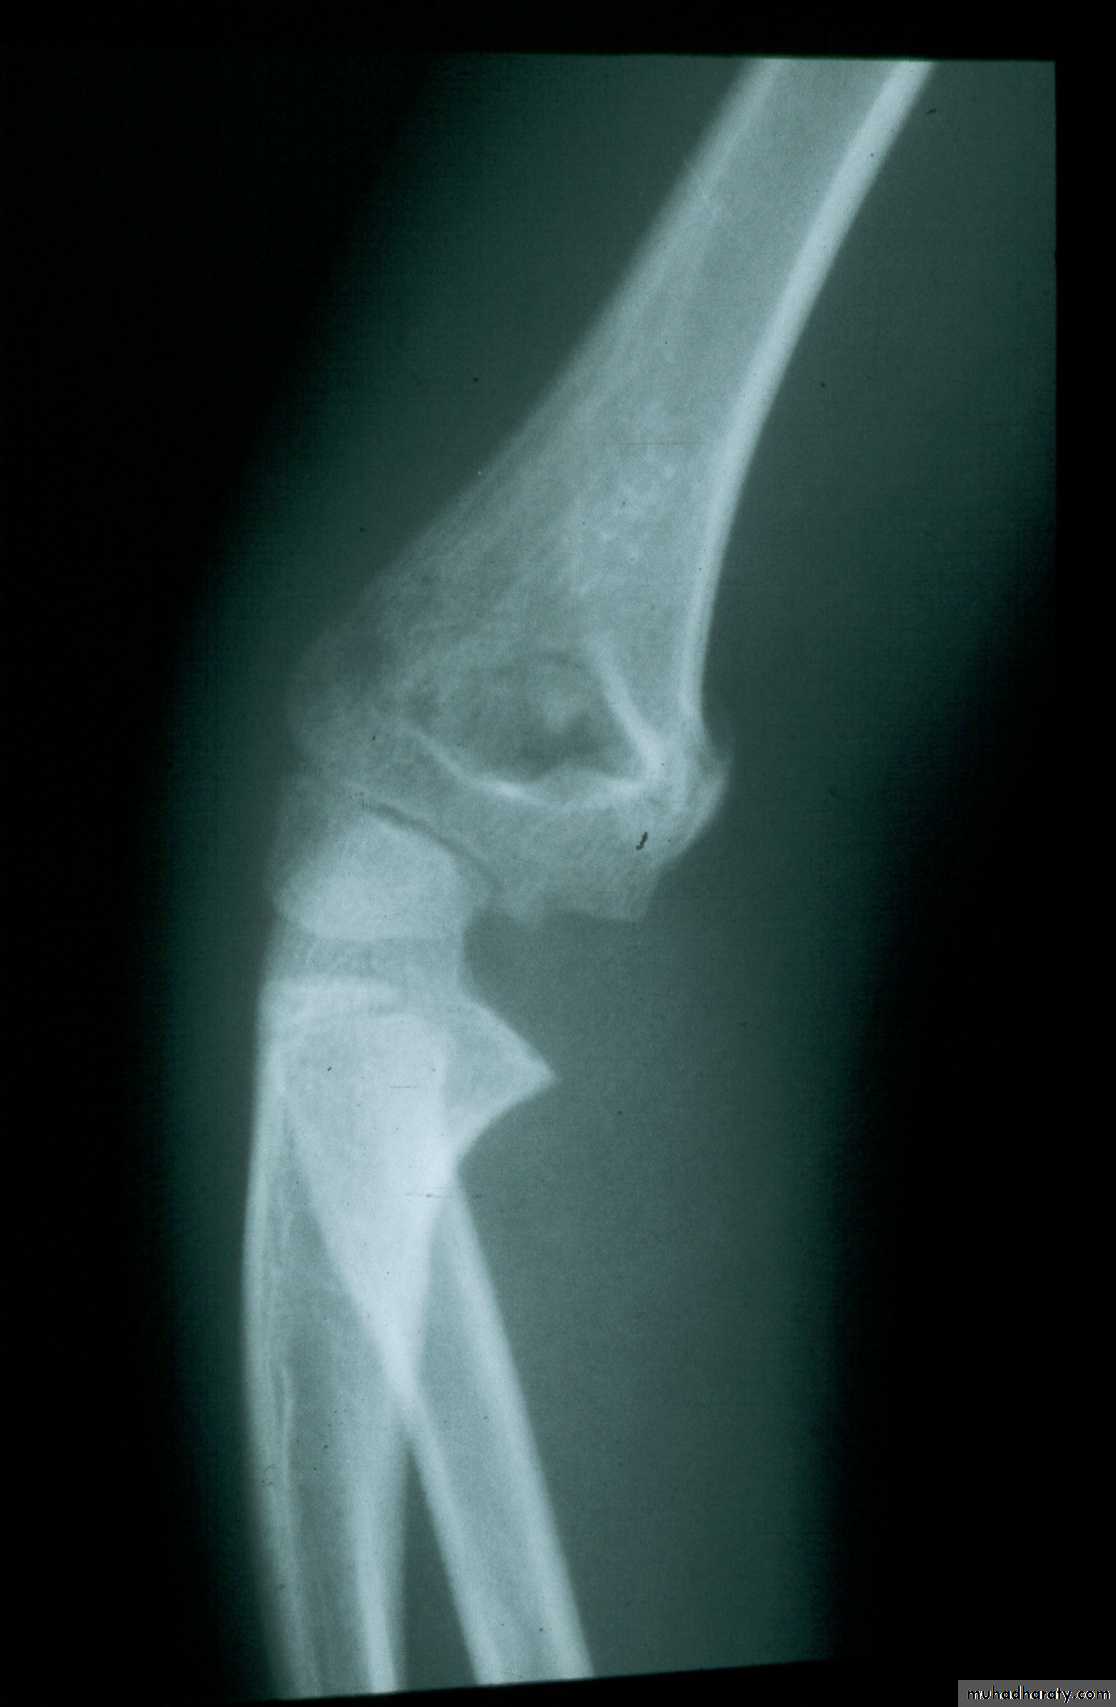

Five y.o. male with this fracture pattern

• Following obtaining a satisfactory closed reduction how do you propose to stabilize it?Multiple lateral pins

Stable ??Five y.o. male with this fracture pattern

• Following obtaining a satisfactory closed reduction how do you propose to stabilize it?

Medial-lateral

retrograde cross pinsDifficult and unstable